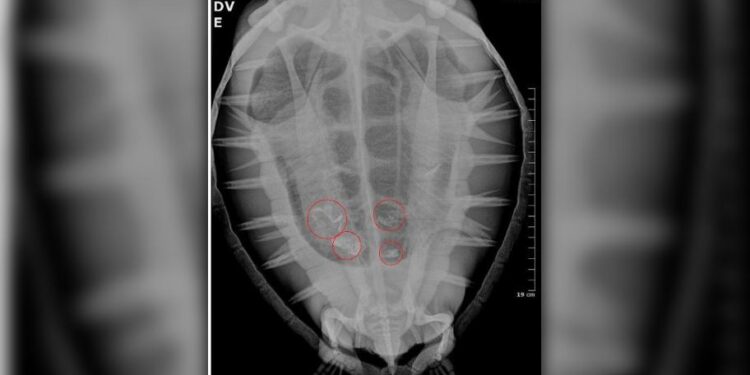

Durante o inverno, período em que aumenta o número de encalhes de animais migratórios, a equipe do PMP-BS registrou casos de tartarugas com ingestão de resíduos.

“Infelizmente, acabamos atendendo vários animais marinhos com plástico, tanto fragmentos rígidos quanto embalagens maleáveis. Já tivemos casos em que o animal chegou vivo ao CReD, mas não resistiu”, afirmou a médica veterinária Carolina Jorge.